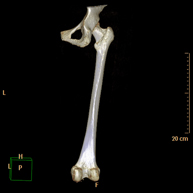

- TC Huesos largos

Exploración radiológica que mediante un sistema de rayos X y detectores que giran alrededor del paciente, reconstruyendo las imágenes por ordenador (TC Multidetector), permite el estudio de huesos largos (tibia, peroné, fémur, húmero, radio y cúbito). - Biopsia ósea guiada por TC